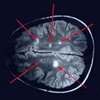

Durante el tratamiento se realizaron resonancias magnéticas cada 4 semanas y los análisis de los resultados fueron los que determinaron que el número de lesiones cerebrales se redujo en un 49 % en los pacientes que fueron tratados con este fármaco, en comparación con los tratados con placebo.